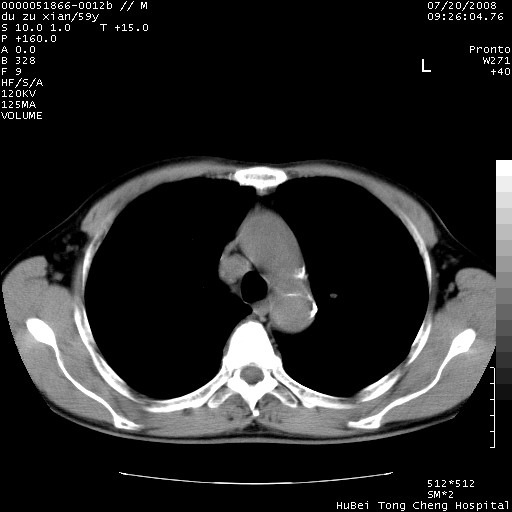

以下是引用宇宙ct在2008-8-25 23:21:00的发言:[br]右肺周围性肺癌并肋骨转移,纵隔淋巴结转移。

以下是引用zsl6918在2008-8-25 22:40:00的发言:[br]右肺周围性肺癌并肋骨转移,纵隔淋巴结转移。

以下是引用zy_zj在2008-8-26 15:24:00的发言:[br]单从病变本身,我倾向良性炎性病变,但肋骨转移了,所以说是考虑右肺周围性肺癌并肋骨、纵隔淋巴结转移可能性大。